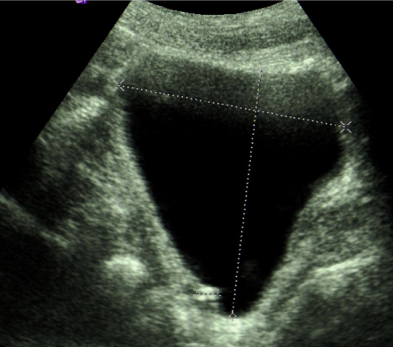

A 70-year-old Caucasian man presented with a three day history of painless gross haematuria associated with storage lower urinary tract symptoms. He is a non-smoker with no family history of bladder cancer. He has a past history of squamous cell carcinoma of the temple, basal cell carcinoma of the eyebrows, plantar fasciitis, rosacea and solar keratosis. Clinical examination was unremarkable. Mid stream urine microscopy and culture confirmed microscopic haematuria and no significant bacterial growth. Urine cytology showed no malignant cells. He had normal PSA, liver function tests, renal function tests, clotting profile and FBC. Ultrasound scan of the kidneys, ureters and bladder showed a 2cm echogenic bladder lesion in the right lateral bladder wall (Figure 1). Cystoscopy showed a 2cm calcified bladder lesion on the posterior wall with another 0.5cm lesion above the trigone (Figure 2). The appearance was highly suspicious of a solid bladder tumor or bladder schistosomiasis. Trans-urethral resection of these two bladder lesions was performed with deep resection. Complete resection was achieved in the smaller lesion but not in the larger lesion due to the density of the calcifications. Bimanual examination under anaesthesia before and after the bladder lesion resection showed no bladder wall thickness or palpable bladder mass. Histology of the resected bladder lesion ruled out bladder malignancy and demonstrated a degenerative eosinophilic material with extensive ossification and accompanying foreign body giant cell reaction in keeping with bladder amyloidosis (Figure 3).

Figure 2 Flexible cystoscopy: 2 cm calcified bladder lesion on the right wall with another 0.5 cm small lesion above the trigon.